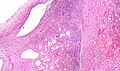

Case 1

| LM | cysts lined by simple epithelium with hobnailing, stroma has an ovarian look (blue, spindle cells) |

- Cysts lined by simple epithelium with hobnailing - key feature.

- Stroma has an ovarian look:

The tumour is predominantly cystic. The cysts are lined by hobnail cells. Ovarian-like stroma is present.